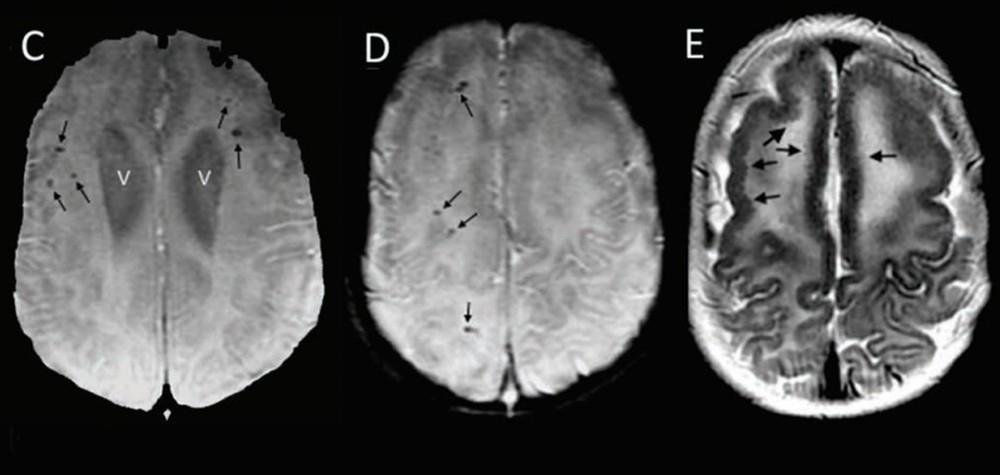

“Destes, 11 desenvolveram microcefalia mais tarde”, afirmaram os cientistas. “Este crescimento anormalmente lento da cabeça foi acompanhado por sérias complicações neurológicas”. Segundo o estudo, a desaceleração do crescimento da cabeça foi verificada a partir do 5º mês de idade, no mínimo.

Sete dos 13 bebês sofreram de epilepsia e “todos tinham problemas de motricidade similares aos de uma paralisia cerebral”, acrescentou o estudo.

Os pesquisadores já sabiam que o zika podia causar problemas no desenvolvimento cerebral mesmo quando não havia sinais externos de microcefalia. Mas o novo trabalho é o primeiro a mostrar o desenvolvimento dos sintomas após o nascimento.

“Uma microcefalia pode não ser evidente no nascimento, mas se desenvolver mais tarde com anormalidades cerebrais subjacentes”, disse o estudo.